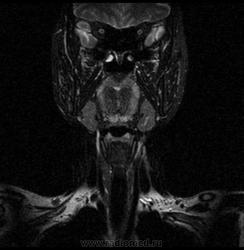

06.06.2011 МРТ - головы и шеи.

Пацентка 36 лет, с жалобами на припухлось в околоушной области справа.

В глубокой доле  правой околоушной железы  на фоне неизмененной паренхимы зона  гетерогенного по Т2, гипоинтенсивного по Т1  с единичными гиперинтенсивными включениями.При контрастировании- накопление контраста диффузное неоднородное и по периферии.Рискну предположить злокачественное образование ( аденокарцинома) с низкой степенью злокачественности( есть капсула, экспансивный рост).Сильно не расстреливайте.

Проблема в том, что перед челюстно-лицевым хирургом стоит распространенность любого объемного процесса, в данном случае все упирается в возмможную травму лицевого нерва и конечно же с дальнейшим его парезом, а ведь женщина  еще молодая. Образование имеет тонкостенную оболочку, по структуре неоднородно, с наличием кальцината, при этом МР-сигнал от окружающих анатомических структур(как костных так и мышечных) не изменен, т.е. об инфильтративном росте речи не идет, в какой то степени доброкачественное. В конкретном случае лицевой нерв с ретромандибулярной веной просто несколько оттеснен.

По гистологии аденома околоушной слюнной железы, но после удаления пока сохраняется парез лицевой мускулатуры, возможно временный.